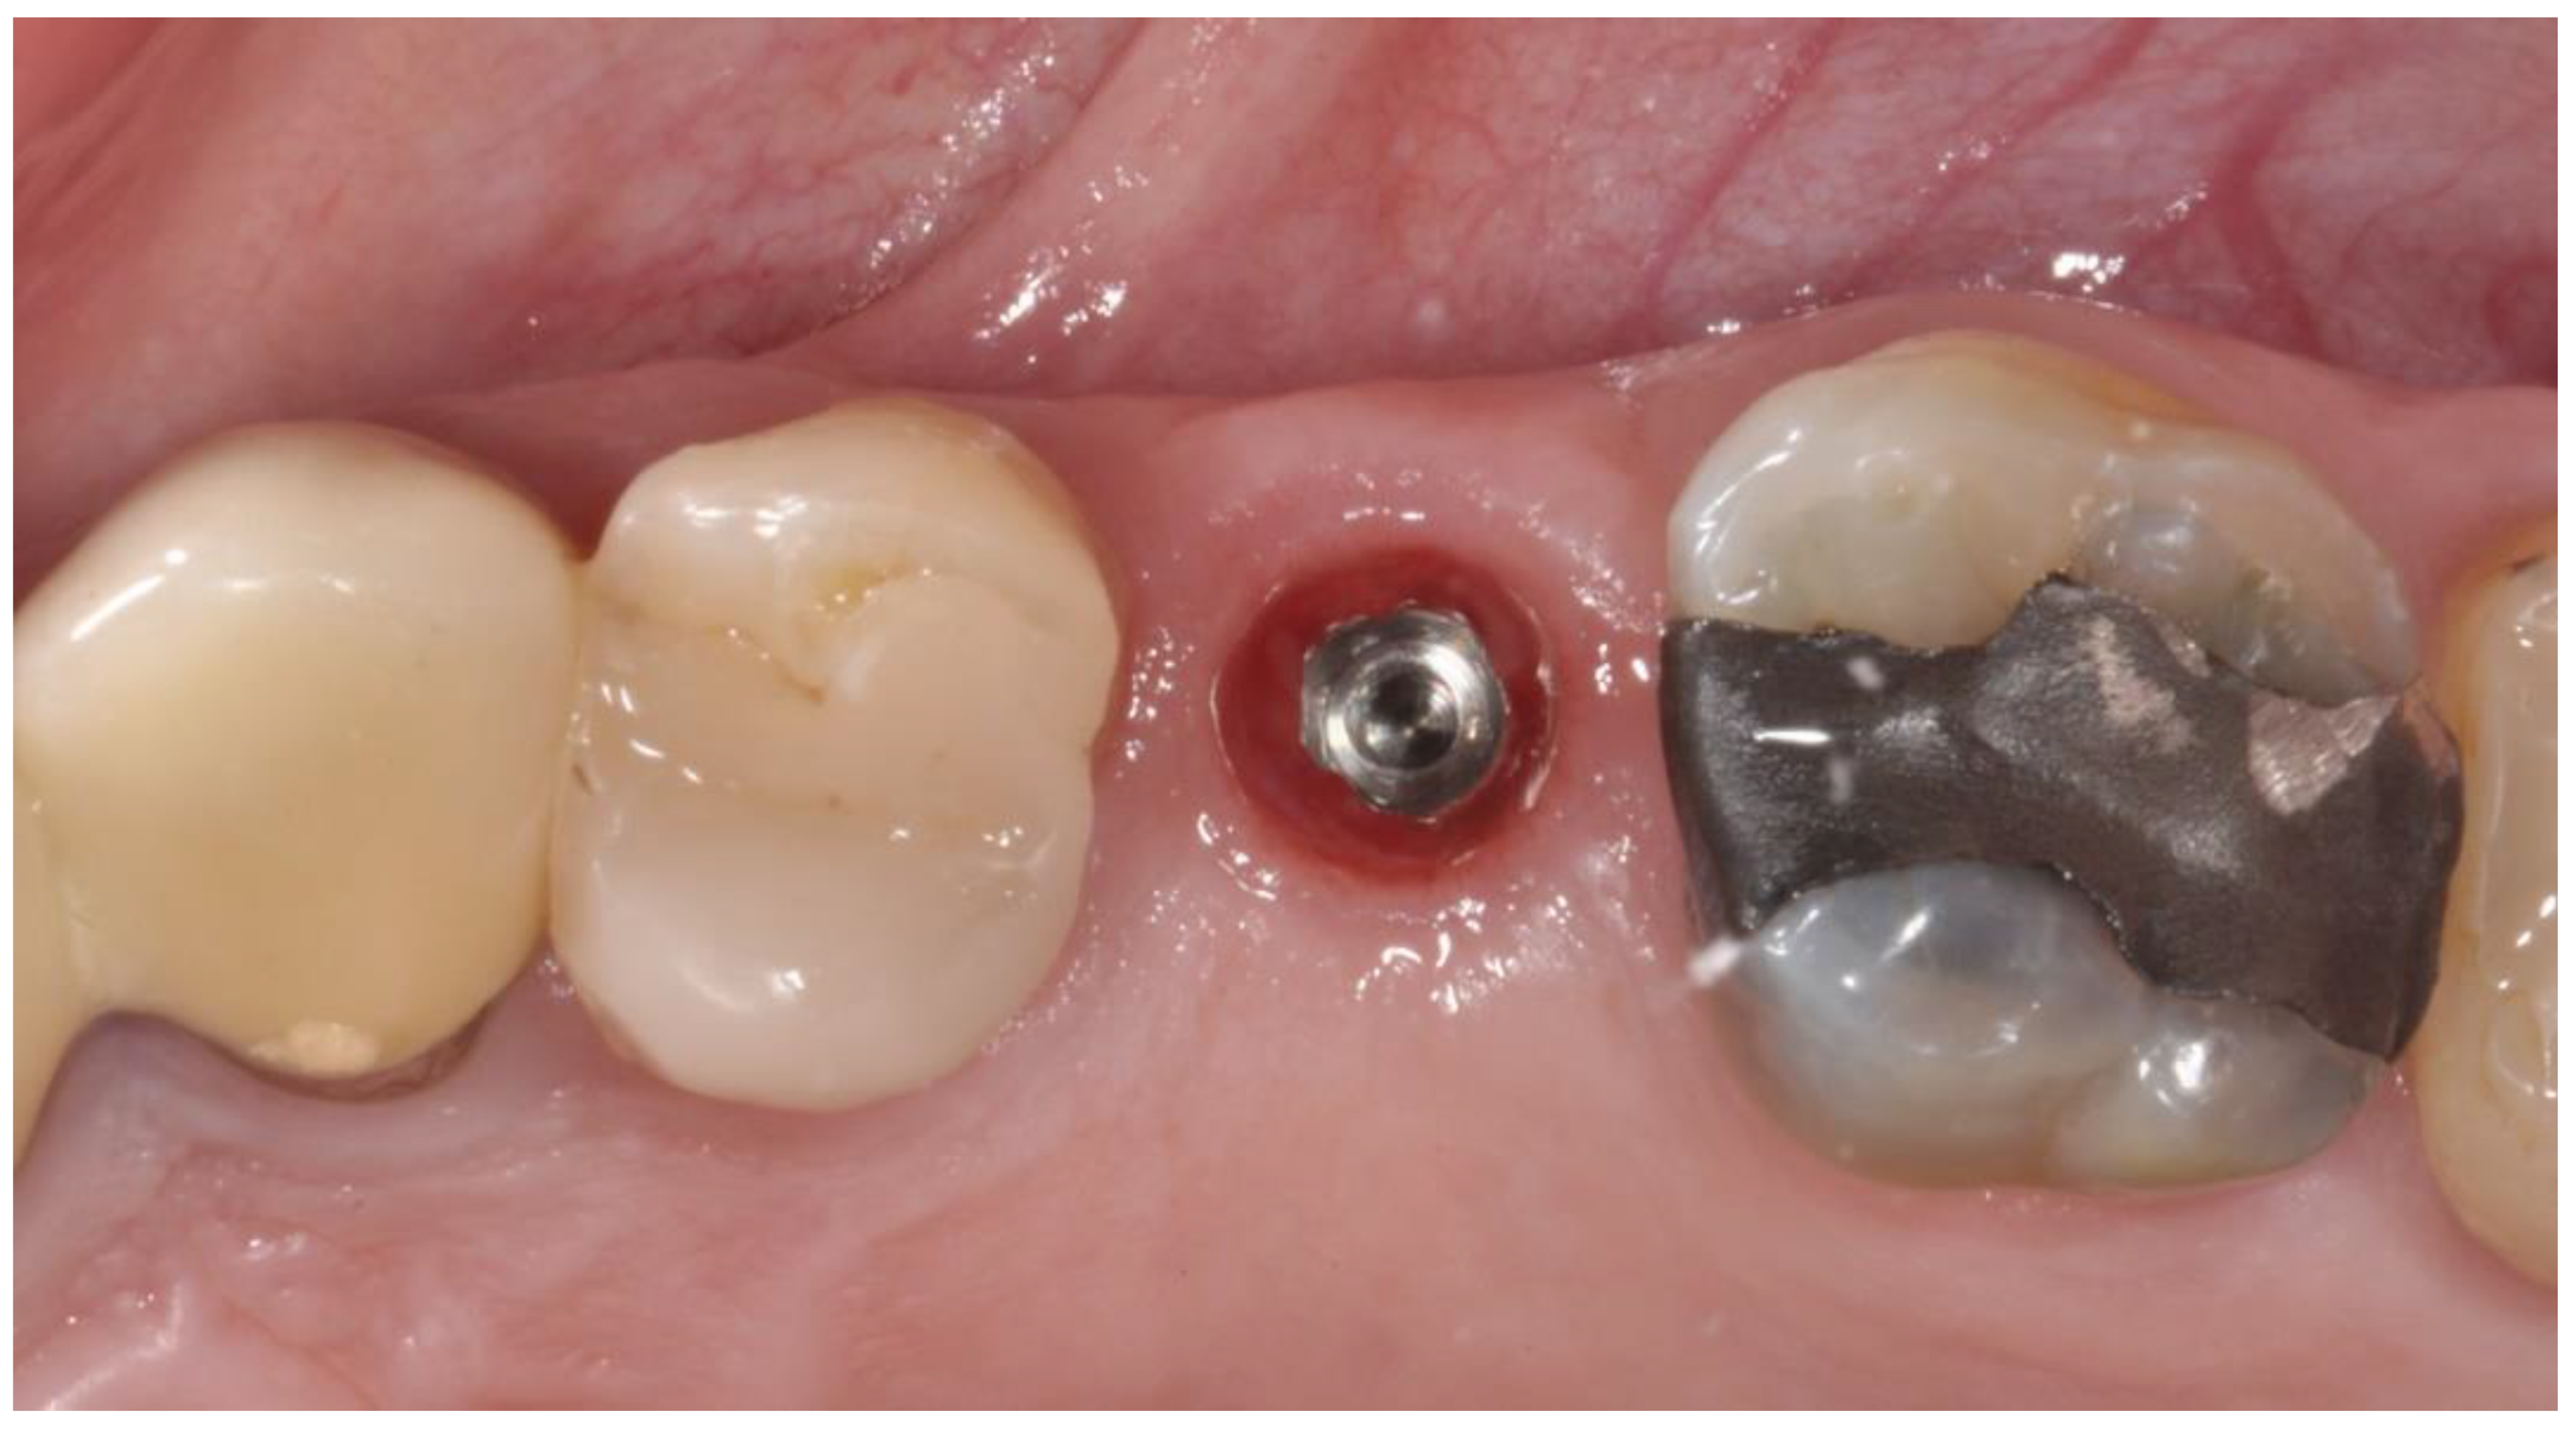

2.2. Surgical Procedures